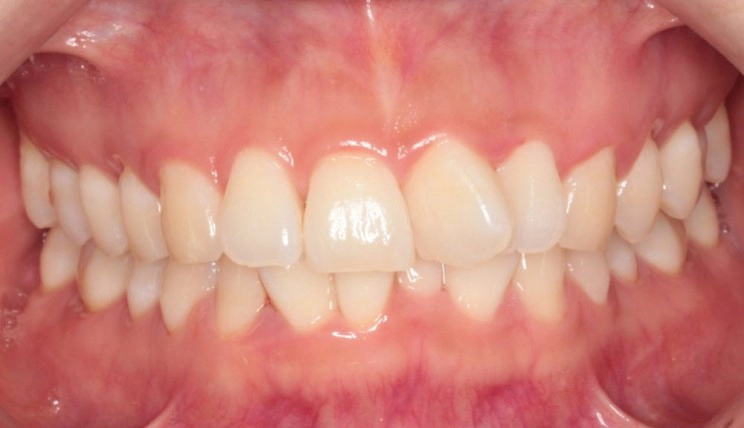

Cắn sâu

Cắn sâu là tình trạng mà sự phủ theo chiều dọc của các răng cửa ở khớp cắn trung tâm lớn hơn 30 – 40%.

Thông tin bệnh nhân:

Tuổi: 13

Giới tính: Nam

Lựa chọn điều trị Invisalign: Invisalign Comprehensive

Tổng thời gian điều trị:

24 tháng